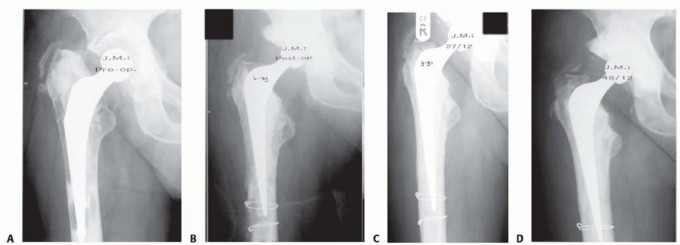

DEFINITION High tibial osteotomy (HTO) is realignment surgery, which has developed for treating medial compar…